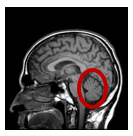

Les figures représentent :

Les conséquences d’une section spinale au niveau thoracique

La moelle épinière